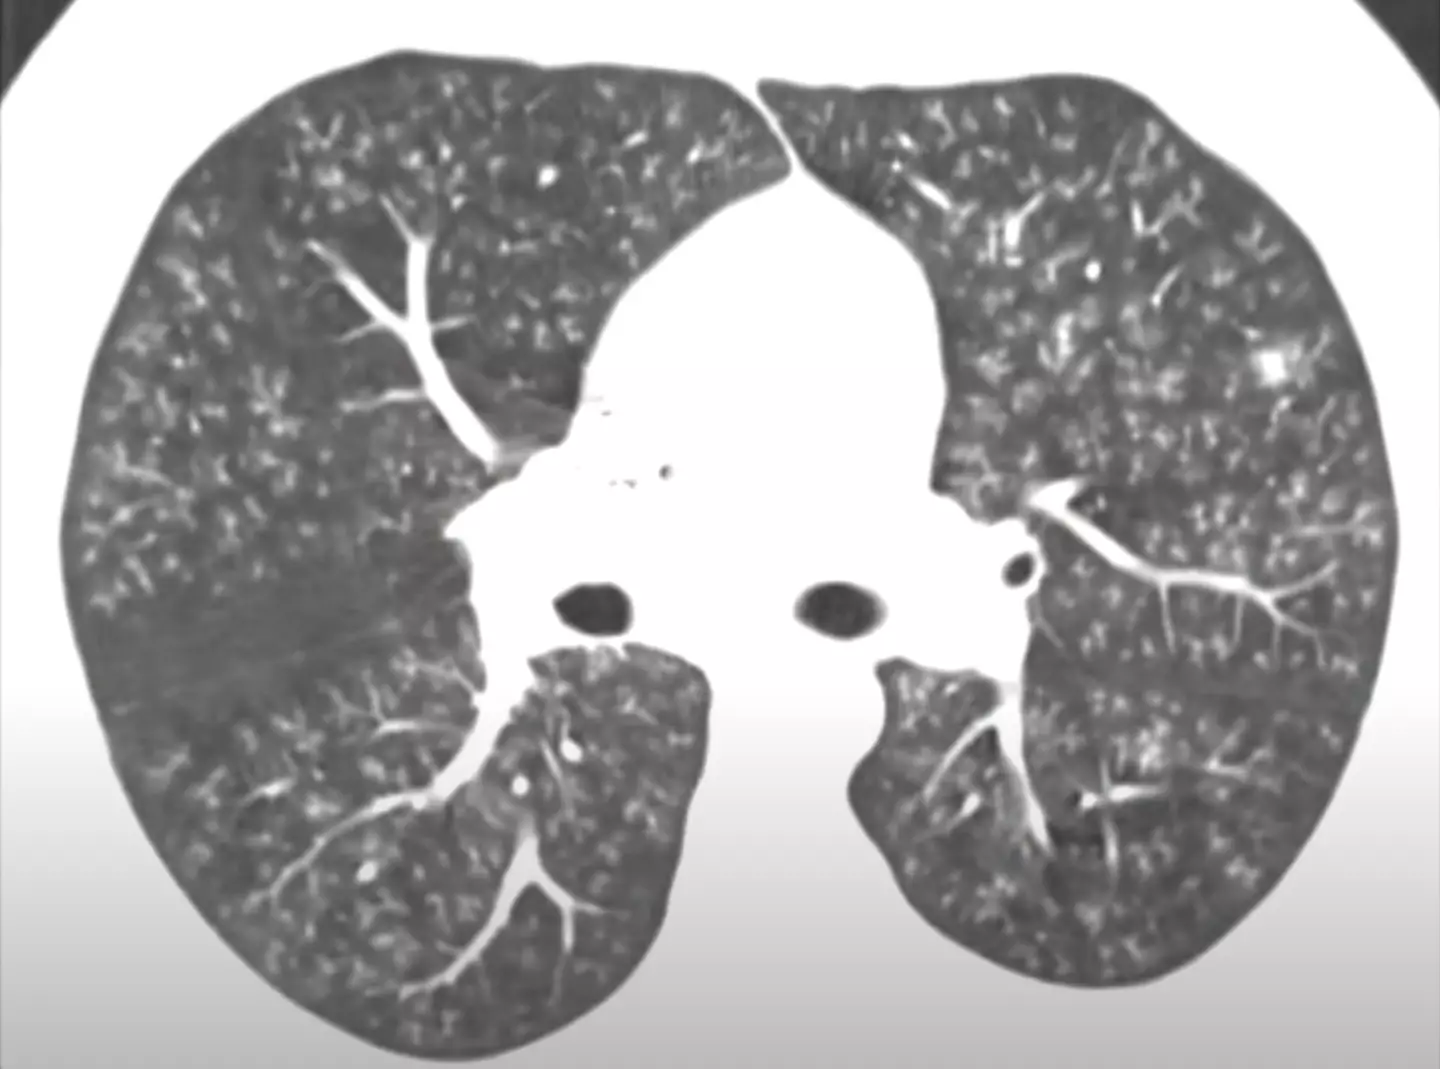

Popcorn lung is the popular name for a condition called bronchiolitis obliterans, which is a rare form of disease that sees scarring and inflammation of the bronchioles, the lung's smallest airways.

Once the airways become inflamed they are no longer able to expel carbon dioxide from the lung, which can lead to a fatal build up. This differs from other vaping or smoking related illnesses which usually occur in the lung's alveoli.

Symptoms of popcorn lung can include shortness of breath, wheezing and coughing which can flare up with exercise or exertion.